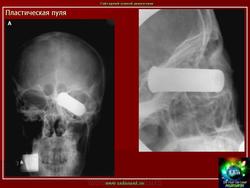

Огнестрел и военные действия.

1.pulya_.29.i.slayd28.jpg2yupulya.30.i.slayd29.jpg3.pulya_.32.i.slayd31.jpg4.pulya_.33.i.slayd32.jpg